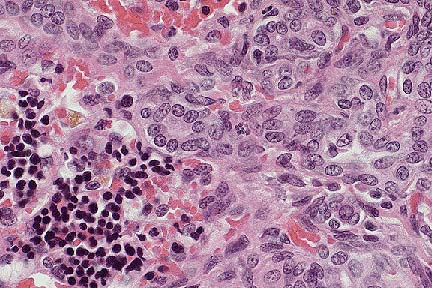

Sarcomatous pattern with prominent collagenous stroma in a mesothelioma in a Hanoverian gelding. (HE, 400X, 51K)

Histologically, the periphery of nodules consisted of epithelioid neoplastic mesothelial cells with squamous, cuboidal or columnar appearance forming papillary projections. In these cells, mitotic figures were frequent. Cells often sloughed from the surface of the nodules into the abdominal lumen. Occasionally, binucleated cells were observed. Inflammatory cells were diffusely scattered throughout the neoplastic tissue. The neoplastic nodules were well vascularized. The centers of the projections consisted of neoplastic mesothelial cells which were fibroblastic to mesenchymal in appearance. In some areas, there was an abundant accumulation of extracellular matrix.

Ultrastructurally, the cells in the periphery of the nodules had numerous microvilli and desmosomes. Within the nodules, neoplastic mesothelial cells were located in a collagen-rich matrix. The tissue had a sarcomatous appearance. These cells formed desmosomes as did the epithelioid neoplastic mesothelial cells in the periphery.

Peritoneal mesotheliomas are rarely seen in horses. In animals they are most frequent in cattle. Mesotheliomas arise from cells of mesodermal origin and grow in an epithelioid and mesenchymal pattern, as observed in the present case. The neoplasm must be classified as malignant because of its widespread occurrence on all abdominal serosal surfaces and the number of mitotic figures in the nodules. However, the tumor did not invade the underlying tissue and there was no metastasis to regional lymph nodes. Human mesotheliomas are classified as epithelial, sarcomatous and biphasic (mixed) depending on the predominant histological feature. In the present case, both epithelial and mesenchymal characteristics were observed. The tumor was, therefore, classified as malignant biphasic peritoneal mesothelioma.

AFIP Diagnosis: Serosal surface and attached skeletal muscle: Mesothelioma, Hanoverian, equine.

Histologically, mesotheliomas exhibit a broad spectrum of patterns from mostly epithelioid to predominantly fibrous. The most common pattern consists of neoplastic cuboidal epithelioid cells covering papillary projections of neoplastic spindle cells which form a fibrovascular core. The fibrovascular core may appear sarcomatous and contains an extracellular matrix that is weakly metachromatic with Alcian blue, methyl violet, or toluidine blue stains. The metachromatic staining is lost after digestion with testicular hyaluronidase; therefore, the material is most likely hyaluronic acid. Ultrastructurally, neoplastic mesothelial cells have a prominent basal lamina, well developed microvilli, desmosomes, abundant rough endoplasmic reticulum, and mitochondria. Immunohistochemical staining is positive for keratin and sporadically positive for vimentin.